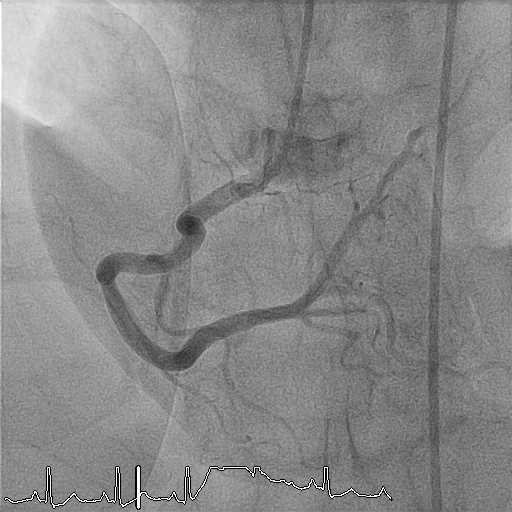

Pre-dilatation was performed with an IKAZUCHI ZERO 2.5 ¡¿ 15 mm balloon at 9–12 atm. Given the massive thrombus burden and prior incomplete systemic streptokinase infusion, intracoronary streptokinase was administered via the aspiration catheter in 1-mL aliquots (15,000 IU each), slowly over 1–2 minutes per dose, to a total of 150,000 IU. Progressive improvement in thrombus dissolution was observed with restoration of distal flow.Following thrombus resolution, direct stenting of the proximal LAD was performed using a Xience PRO-A 3.0 ¡¿ 23 mm drug-eluting stent, deployed at 9 atm. Post-dilatation was performed with a CONQUEROR NC 3.0 ¡¿ 15 mm balloon at 12–20 atm achieving full stent expansion. Final angiography demonstrated TIMI 3 flow with no dissection or residual stenosis.Given reduced LV systolic function, an IABP was inserted via the right femoral artery for hemodynamic support. Total contrast volume was 120 mL, total fluoroscopy time 10.03